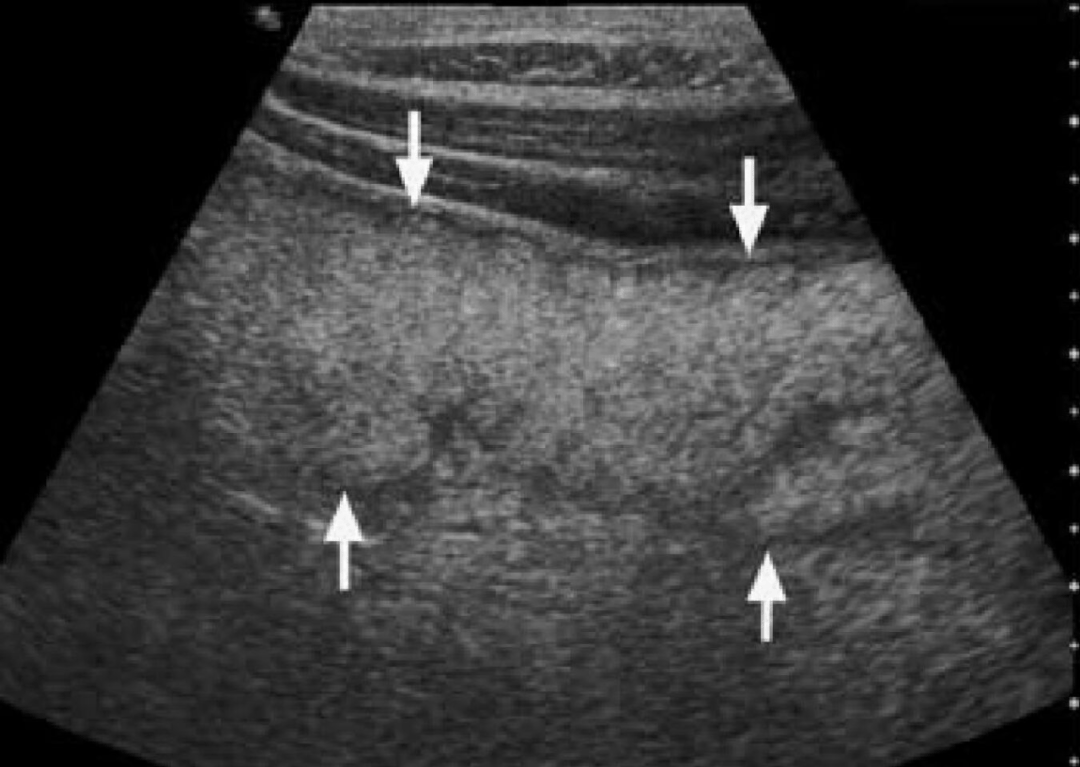

图4-6:Whipple病的“白肠、白淋巴结”。病例2,患者,男性,54岁,反复腹痛、腹泻、脂肪泻、关节痛。超声显示空肠段肠壁全层几乎呈弥漫性高回声(箭头所示),仅外层肌层呈薄层低回声带。同时,在肠系膜血管旁可见明显增大的高回声淋巴结(△所示),直径约20mm。该病例后经十二指肠活检确诊为Whipple病。Hint:这种“高回声肠壁-高回声淋巴结”的组合被认为是Whipple病的相对特征表现,而与之相应,Whipple病的病理特征即为肠黏膜及淋巴结内大量泡沫状巨噬细胞(含PAS阳性物质)浸润,这是产生高回声的基础之一。